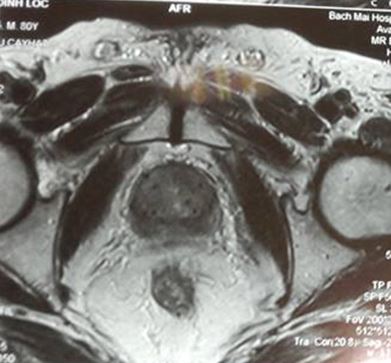

- Chụp MRI: Không thấy khối bất thường trên hình ảnh MRI tiểu khung

- Xét nghiệm PSA toàn phần tiếp tục giảm xuống còn 0,91 ng/ml, PSA tự do 0,15 ng/ml.

Trước điều trị: khối u tuyến tiền liệt ranh giới rõ, bắt thuốc mạnh, kích thước 15 mm, chưa xâm lấn vỏ bao và túi tinh 2 bên; PSA = 28,5 ng/ml

Sau điều trị 7 tháng: không còn u trên cộng hưởng từ, nồng độ PSA về bình thường, bệnh nhân hết đi tiểu khó, thể trạng tốt; PSA giảm xuống rất nhiều còn 0,91 ng/ml.

• Chụp MRI: Không thấy khối bất thường trên hình ảnh MRI tiểu khung

• Xét nghiệm PSA toàn phần tiếp tục giảm xuống rất thấp còn 0,26 ng/ml, PSA tự do 0,01 ng/ml.

Trước điều trị: tiểu són, tiểu nhiều lần; trên cộng hưởng từ khối u kích thước 12 x 15 mm, ranh giới không rõ, chưa xâm lấn vỏ bao và túi tinh; PSA = 2,4 ng/ml

Sau điều trị 7 tháng: thể trạng tốt, đi tiểu bình thường; trên hình ảnh cộng hưởng từ không có khối bất thường; PSA giảm xuống còn 0,26 ng/ml